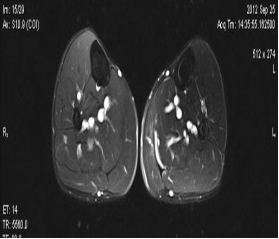

典型病例:患者,男,40岁,体能训练致左小腿肌肉撕裂伤并巨大血肿,给予脉冲磁疗、中频电疗和下肢肌肉训练指导后,血肿逐渐消退,两个月后肌肉恢复正常,继续参加训练。